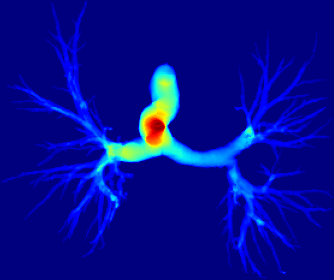

However, current state-of-the-art methods of lung organ segmentation still face several challenges and aspects for improvement. Firstly, the unlimited voxel values, multi-site imaging discrepancy and class imbalance in lung organ images can lead to false-negative and leakage issues in prior segmentation methods, which badly influences the critical early diagnosis of imperceptible lung diseases, e.g., lung fibrosis, nodule and hypertension, etc. Secondly, the presence of numerous slender branches, e.g., bronchioles and arterioles, which are easily lost during the recycled down/up-sampling procedure in Fig. 1, can result in discontinuity, detail loss, and coarse mask predictions. Thirdly, most CNN-based medical segmentation methods treat all points equally during the mask rendering stage, overlooking the vulnerability of border points in Fig. 1 (f) and the importance of explicit border modeling. Lastly, while Vision Transformer (ViT) has shown promise in computer vision tasks [1, 4], its quadratic operation complexity limits its application in 3D high-resolution CT images due to hardware constraints. Meanwhile, most specific datasets for medical image analysis are small and scarce due to laborious manual annotation and privacy protection, which badly restricts the potential of transformer-based top-tier methods.

2.2 Global-Local Cube-tree Fusion

where [0, 1] are the learnable coefficients to balance the importance of each feature; (6) we lastly add the feature to the relative position embedding features (retaining the topology information for inductive bias) for the voxel-wise decoding and refined prediction. Obviously, our proposed global-local cube-tree fusion module focuses merely on all border vulnerable points in Fig. 1(f) rather than all regular dense points in Fig. 1(c), which is more related to the lung organ regions. Experimental results demonstrate the efficacy of this design.